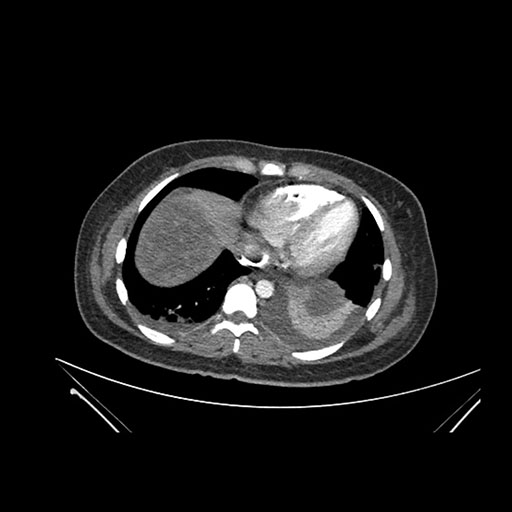

Imaging Analysis

Look through the patient's CT scan to identify any areas of concern for the necessary procedure.

Axial Arterial

Based on initial findings, which issue(s) would you be most concerned about?